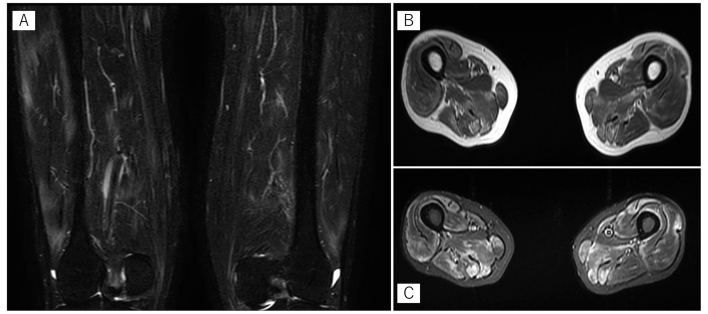

Myositis-specific autoantibodies play an important role on the disease phenotype of idiopathic inflammatory myopathies (IIMs). Anti-signal recognition particle (SRP) antibody-positive patients with IIMs may present with severe myopathy and highly elevated serum creatine kinase levels. These patients are often resistant to immunosuppressive therapy, but there is no established treatment strategy. A 51-year-old man referred to our department was diagnosed with IIM based on imaging and pathological findings. A high dose of corticosteroids followed by intravenous cyclophosphamide (IV-CY) treatment (750 mg three times) resulted in an improvement in clinical manifestations and functional outcomes, and recurrence did not occur. Our case suggests that IV-CY is an effective induction regimen for patients with anti-SRP antibody-positive IIMs.